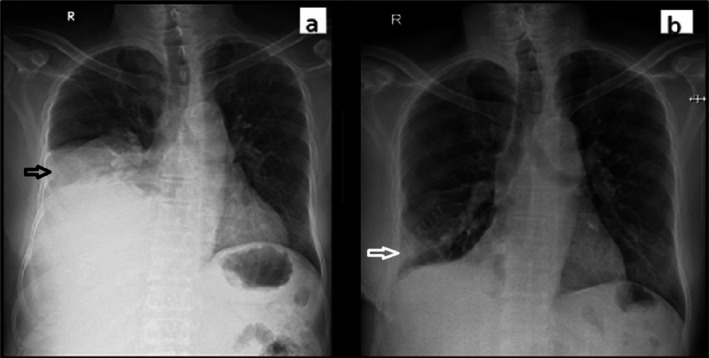

孤立性纤维性肿瘤(SFTs)是罕见的梭形细胞肿瘤,主要是良性的,占所有软组织肿块的不到2%。在极少数情况下,SFTs可导致doge - potter综合征,这是一种副肿瘤疾病,其特征是由于胰岛素样生长因子II (IGF-II)水平升高而导致低血糖。患者通常表现为与这种激素失调有关的症状性低血糖。我们报告一例70岁的男性,他表现为体重减轻,咳嗽,疲劳,刺痛,以及与复发性低血糖相关的精神错乱发作。胸片示右下半胸一大块软组织肿块,ct引导下活检证实右下叶基底段肿瘤浸润。

Solitary fibrous tumours (SFTs) are rare spindle cell neoplasms, predominantly benign, comprising less than 2% of all soft tissue masses. In rare cases, SFTs can lead to Doege-Potter syndrome, a paraneoplastic condition characterised by hypoglycaemia due to elevated levels of insulin-like growth factor II (IGF-II). Patients typically present with symptomatic hypoglycaemia related to this hormonal dysregulation. We report the case of a 70-year-old man who presented with weight loss, cough, fatigue, tingling, and episodes of confusion associated with recurrent hypoglycaemia. Chest radiography revealed a large soft tissue mass in the right lower hemithorax, and CT-guided biopsy confirmed tumour infiltration in the basal segment of the right lower lobe.